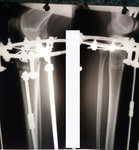

Дата операции 20.07.2018г.

Рентген в 60 дней.

"Сращение идёт отлично! Ждем на снятие аппаратов, через 2 недели."